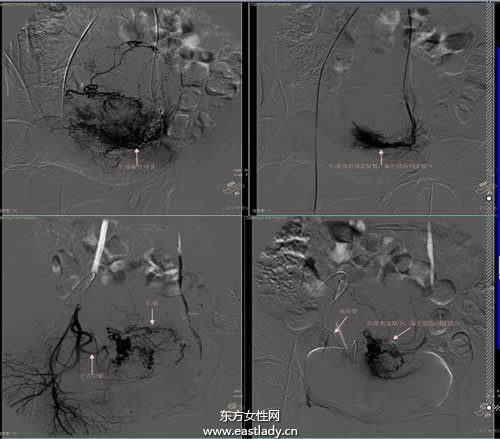

1.介入治疗:介入治疗就是在X线电视、CT、B超引导下,将特制的穿刺针、导管插入肝脏的肿瘤区进行诊断及治疗的一种方法,多以肝动脉化疗栓塞术为主体,疗效较好,且发展也很快,所以身体素质较好的肝癌晚期患者可选用此种治疗方法。